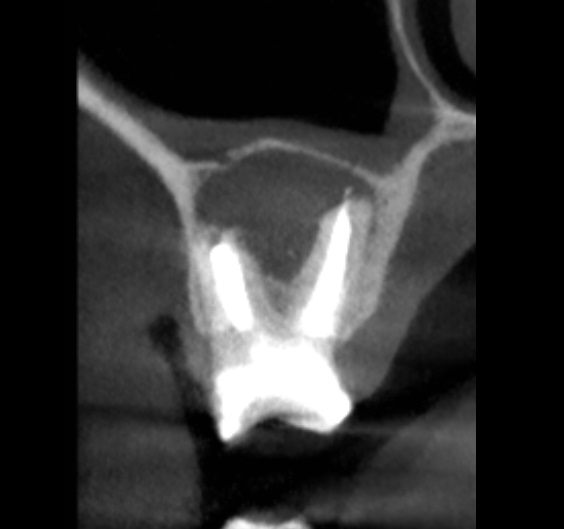

Kanały policzkowe udało się opracować i wypełnić do 1/3 wierzchołkowej, dalsze części kanałów były całkowicie zobliterowane. W trakcie opracowywania kanału podniebiennego zauważono wyciek żółtego opalizującego płynu spoza wierzchołka korzenia zęba, który po kilku minutach samoistnie ustał. Zasugerowało to obecność torbieli korzeniowej. Po zakończeniu leczenia endodontycznego wykonano zdjęcie punktowe kontrole (ryc. 2) oraz tomografię komputerową wiązki stożkowej (cone beam computed tomography – CBCT) opisywanego zęba. Jej rezultat przedstawiają ryciny 3‑6. Widzimy na nich znacznych rozmiarów torbiel korzeniową, która w toku leczenia musi zostać usunięta. Ustalono rozpoznanie ostateczne – torbiel okołowierzchołkowa. Omówiono z pacjentem jego stan i zaproponowano dalsze leczenie, na które wyraził zgodę.

Ryc. 4. CBCT – obraz zmiany w płaszczyźnie czołowej.